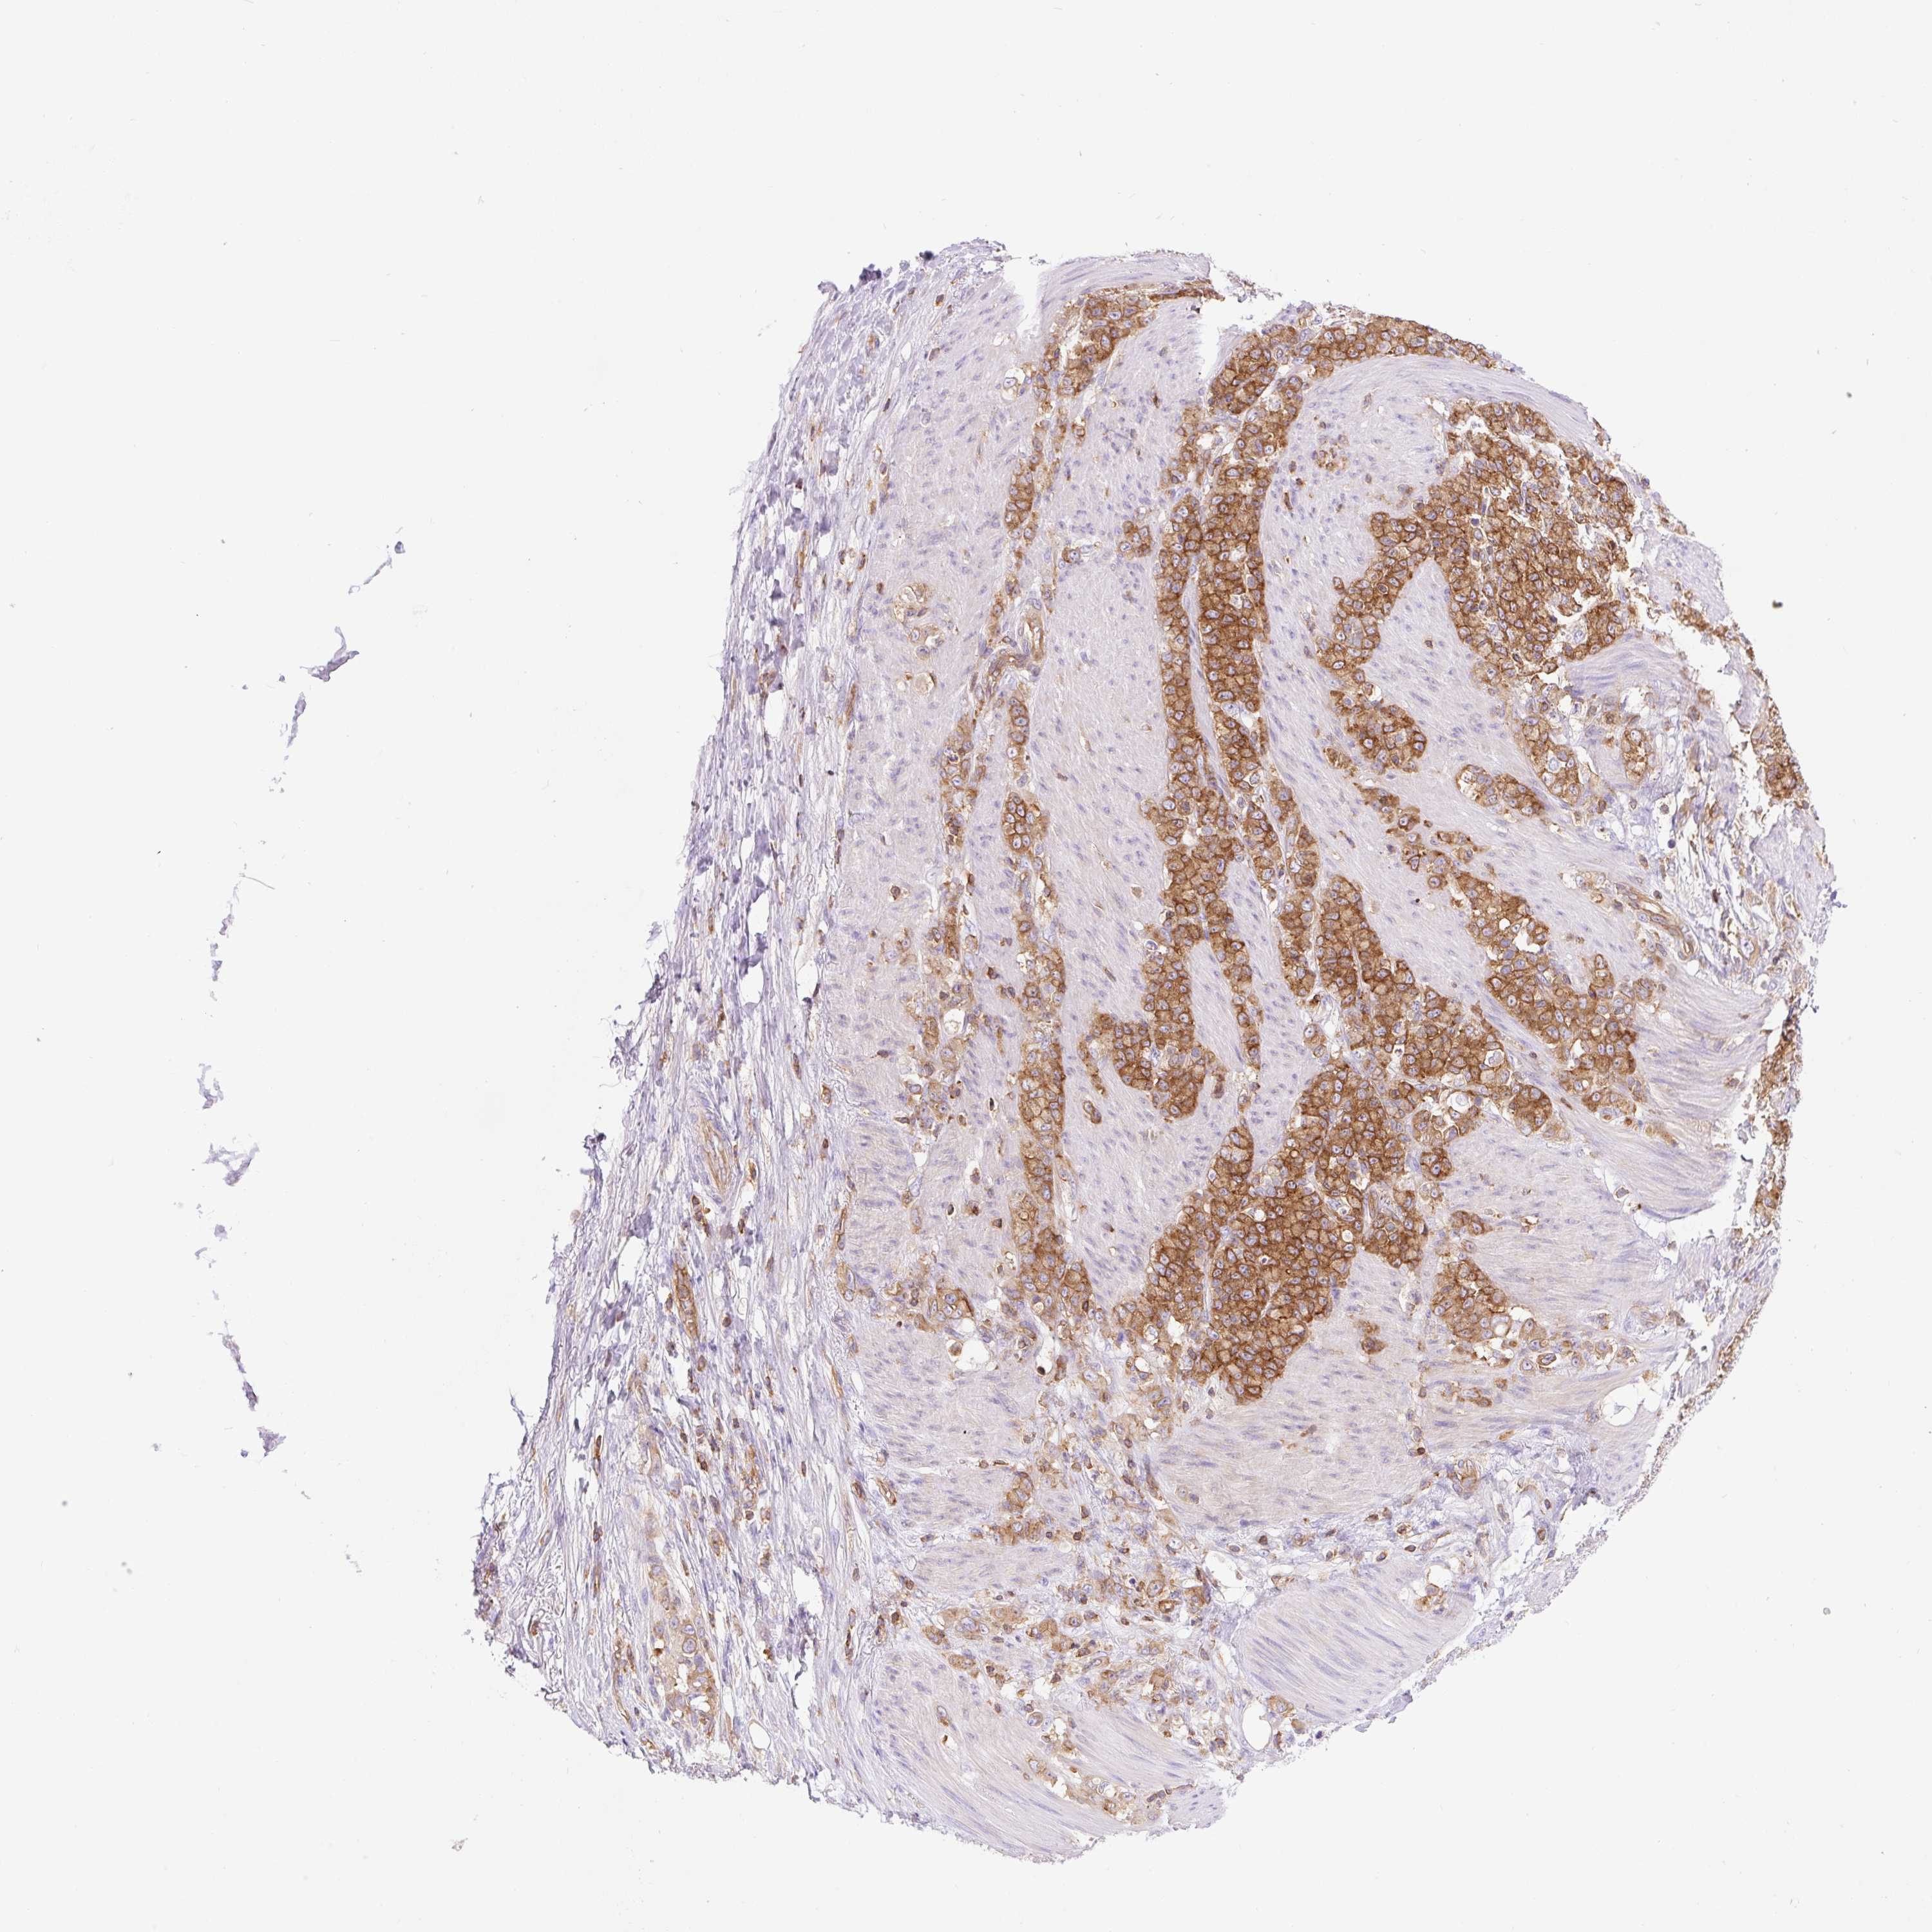

STOMACH CANCER - Protein expressioni

A mouse-over function shows sample information and annotation data. Click on an image to view it in a full screen mode. Samples can be filtered based on level of antibody staining by selecting one or several of the following categories: high, medium, low and not detected. The assay and annotation is described here.

Note that samples used for immunohistochemistry by the Human Protein Atlas do not correspond to samples in the TCGA dataset.

Antibody stainingi

Antibody staining in the annotated cell types in the current human tissue is reported as not detected, low, medium, or high, based on conventional immunohistochemistry profiling in selected tissues. This score is based on the combination of the staining intensity and fraction of stained cells.

Each image is clickable and will lead to virtual microscopy that enables deeper exploration of all samples and also displays staining intensity scores, fraction scores and subcellular localization as well as patient and tissue information for each sample.

Antibody HPA054246

Staining

High

Medium

Low

Not detected

Intensity

Strong

Moderate

Weak

Negative

Quantity

>75%

75%-25%

<25%

None

Location

Nuclear

Cytoplasmic/membranous

Cytoplasmic/membranous,nuclear

Adenocarcinoma, NOS